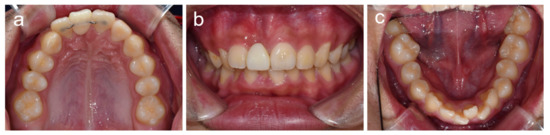

2. Cases

2.1. Case 1

2.2. Case 2

2.3. Case 3

2.4. Case 4

2.5. Case 5